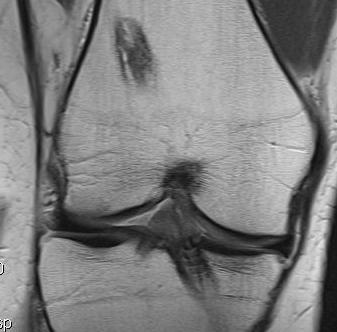

Coronal MRI can see ACL stump remnant, graft not intact. First sagittal confirms tunnel lysis.

Second demonstrates that femoral tunnel is sufficiently posterior